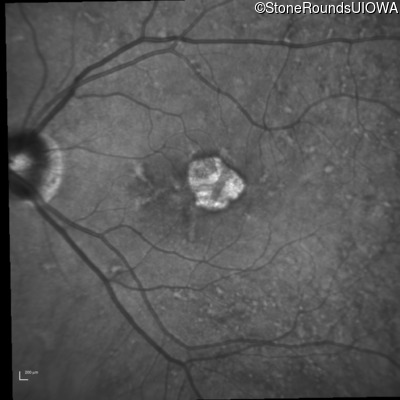

Infrared Fundus Photograph - Right - 20/20

Exemplar